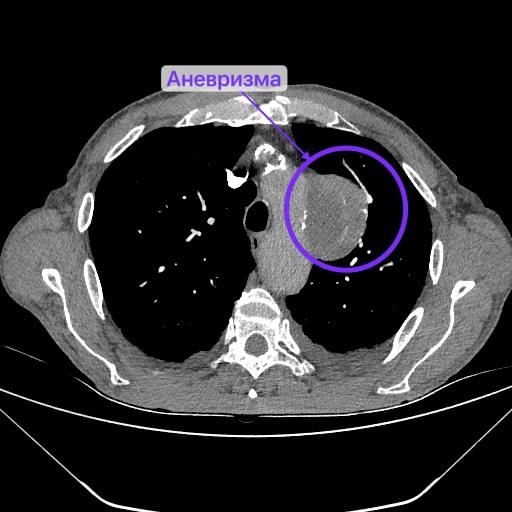

Медик направил мужчину в стационар, где он пролежал три недели. Врачи Нижнекамской ЦРМБ обследовали пациента и обнаружили образование, после чего рекомендовали взять направление к онкологу по месту жительства. Все это случилось под новогодние праздники. Поэтому к онкологу Вячеслав попал только в январе. Оказалось, что за это время в легком развился абсцесс, а на аорте образовалась аневризма.

«Оперировать легкое было опасно, аневризма, как бомба, могла разорваться в любой момент. Поэтому сначала за пациента взялись рентген-хирурги – установили стент-графт (устройство для укрепления стенок аорты), чтобы предотвратить разрыв аневризмы. Стент-графт подбирается индивидуально под каждого пациента. После чего мужчину наблюдали и лечили в отделении сосудистой хирургии. К моменту перевода в торакальное отделение №1 хирурги получили результаты биопсии», — поделились специалисты.